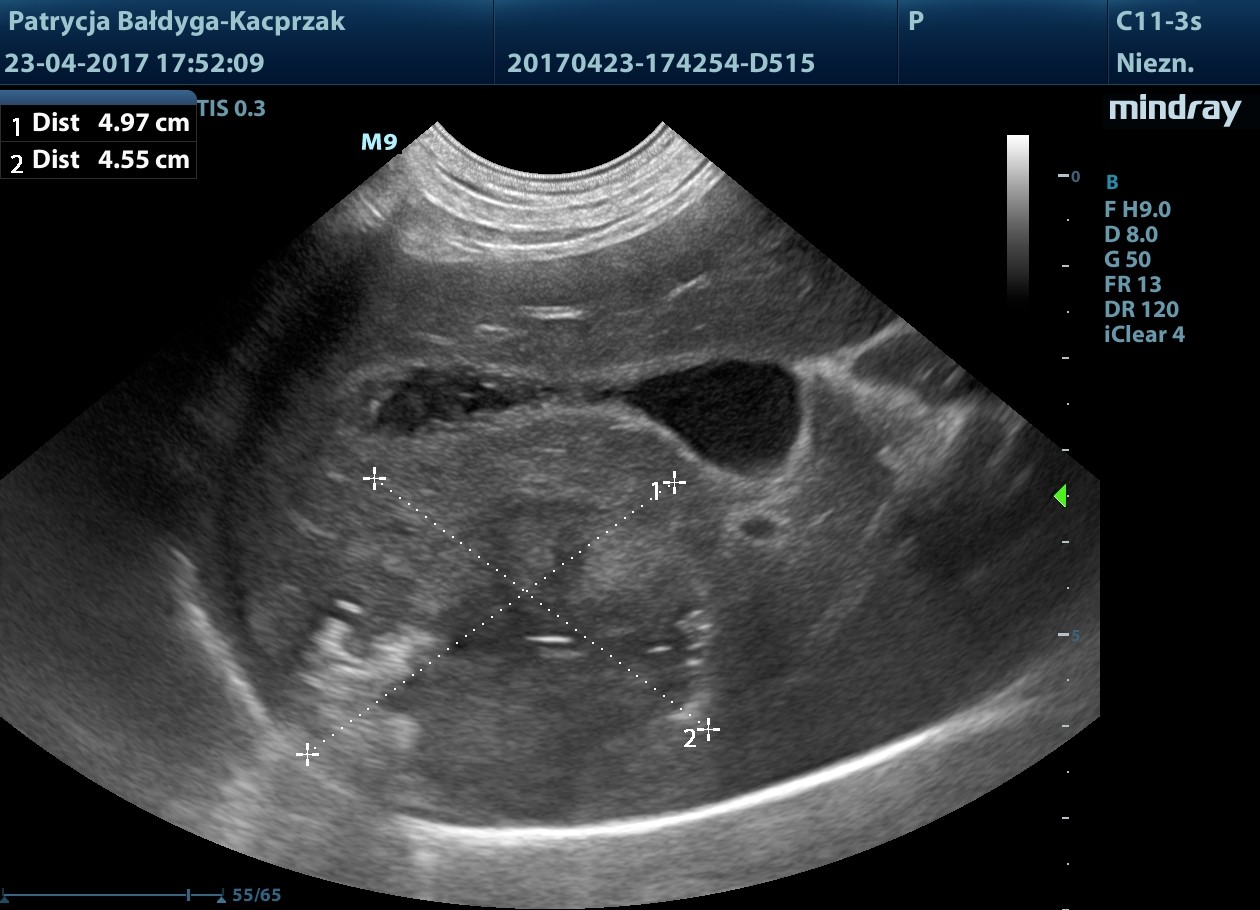

Maj

Widoczne nowe, liczne metastazy w wątrobie, niejednorodnie hiperechogenne, poszczególne wyglądu tarczy, śr. 1-5 cm, modulujące naczynia oraz brzegi narządu.